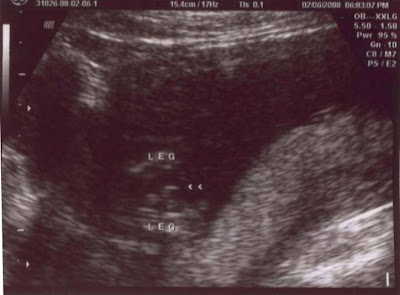

UNOFFICALLY, "It's a Boy!" Today we went for our first ultrasound. This was not done at my doctors office, rather a retail ultrasound studio that lets you take a peek at your bundle of joy. The goal was a gender reading, but because the baby is still so small it was hard for them to get a clear image of with the 3D/4D. We ended up being able to see so much more with the 2D. It was the most amazing experience! Especially when we got to see the profile shots and a clear view of the head, and body... I even saw a little hand waving at us at one point. I am disappointed that we didn't get any snapshots of the profile, because it was really neat. We just ended up with the two you see above. The baby was very active, which also made it difficult for her to get a good shot of the goods- because everytime she thought she had one "he" would move. We are not completly conviced that it's a boy yet, for anyone who knows about our neice- we have good reason to doubt the results. My sister and my aunt were present for the scan, and they were both pretty convinced and sure that they "saw something"... it's just hard to say if that "something" was the goods or an umbilical cord. The ultrasound technician seemed to be "pretty sure" and it was her best educated guess. Either way we are excited we are just disappointed that its not more clear. We have another ultrasound scheduled for February 29th for my appointment at 20 weeks. The baby will double in size by that time so it should be easier for them to get a better reading. So for now, It's a Boy... but who knows? That could change- and hopefully we'll know for sure real soon!